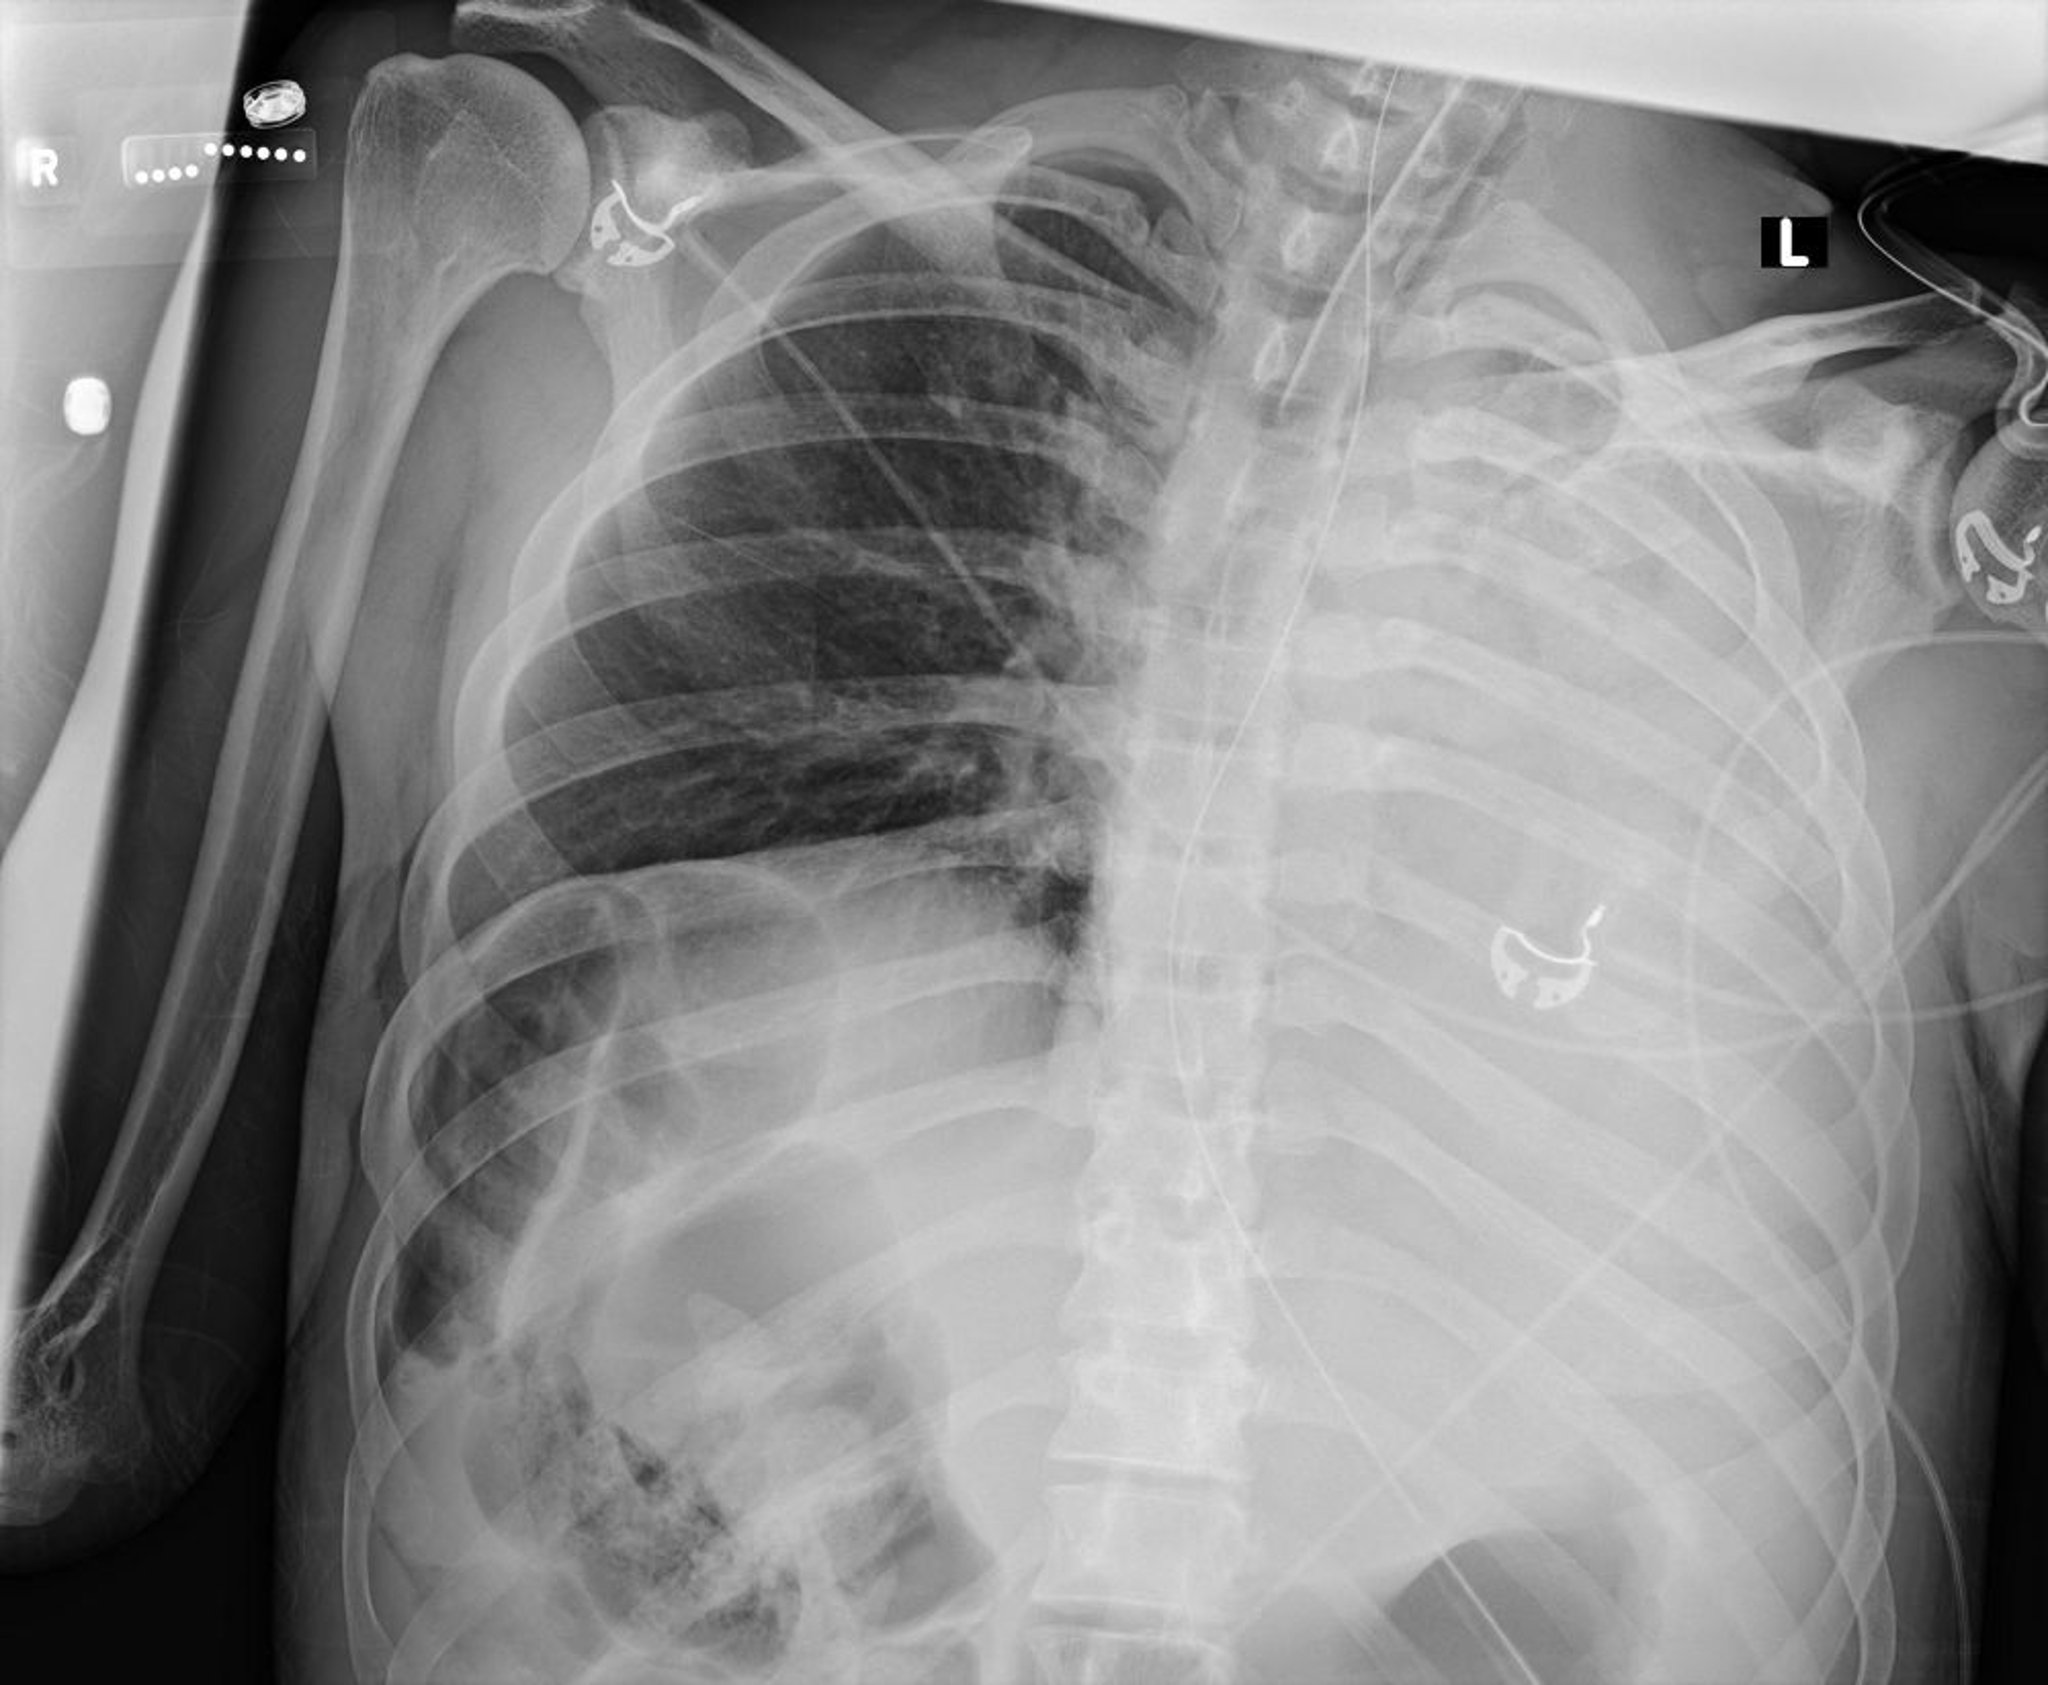

Atelectasia y colapso del pulmón izquierdo (radiografía)

Esta radiografía de tórax muestra el colapso de todos los lóbulos del pulmón izquierdo debido a un tapón de moco.

Courtesy of Alexander S. Niven, MD